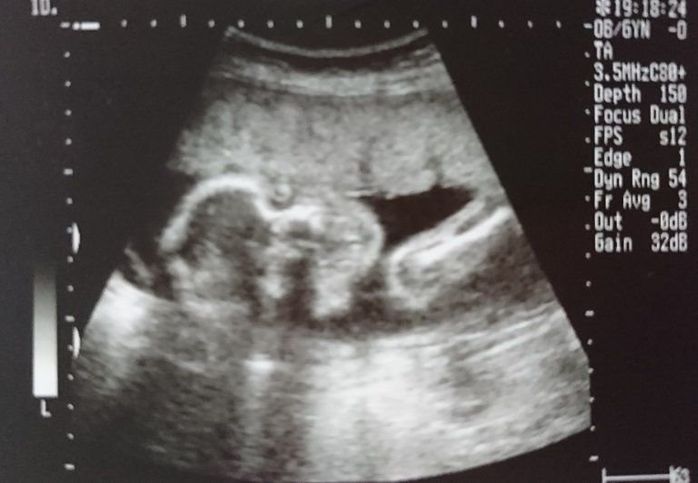

妊娠31週目のエコー写真

ふっくらと顔も体も丸みをおびてきました。3D画像は、横顔がはっきりと写っていて、手をギュっと握っているのが分かります。今の息子の寝顔にそっくりだと、改めて思いました。この頃の体の悩みは、腰痛と脚のむくみでした。家に帰り着圧ソックスを履くとかなり楽になりました。赤ちゃんの推定体重は1648gでした。